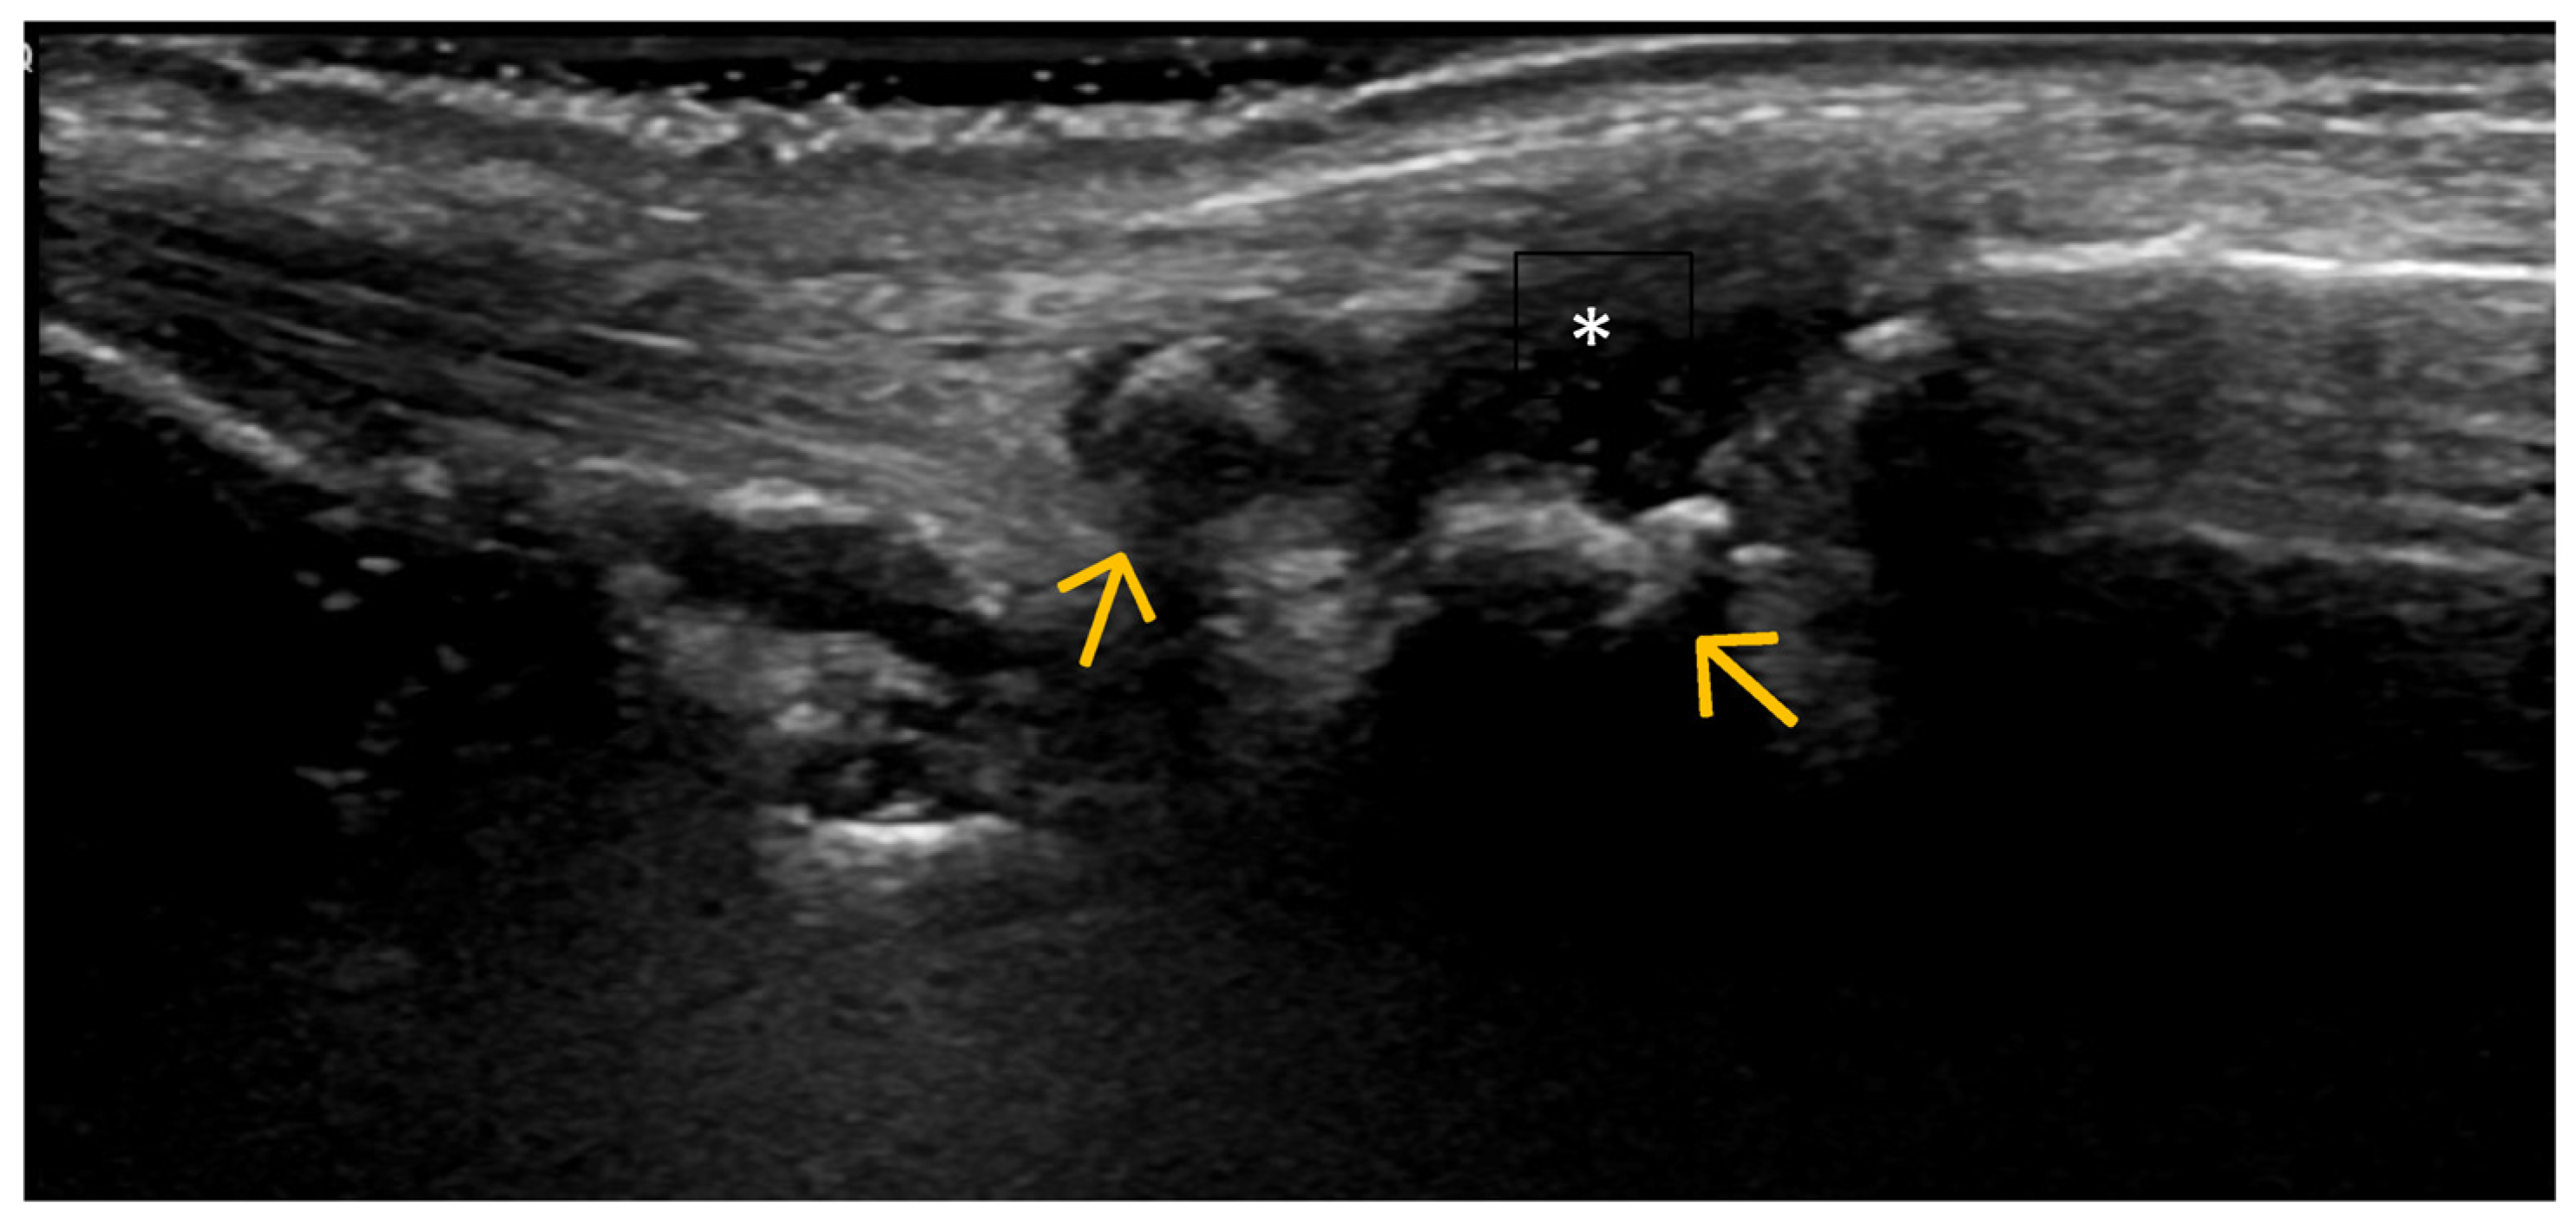

4. Examples of US Phenotypes